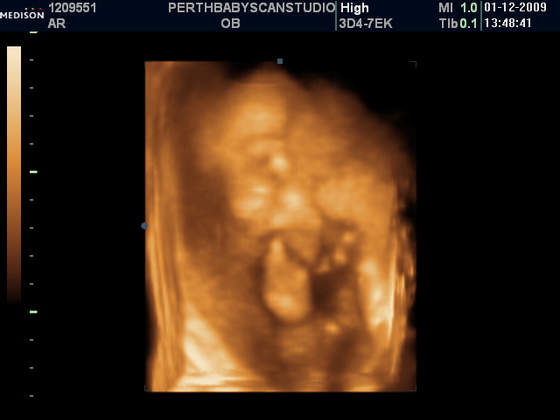

W naszym miescie na polnocy szkocji, o ile nie ma zadnych komplikacji, robia programowo tylko jedno usg (w 13 tygodniu):-(. My bardzo chcielismy znac plec dziecka dlatego pojechalismy do innego miasta (2 godziny drogi) i zaplacilismy £75 za usg ktore mialo byc w 2d ale mila pani doktor zrobila nam prezent na swieta i dostalismy tez zdjatka w 3d (ktore normalnie kosztuja £130) . Teraz przynajmniej wiemy ze bedziemy mieli sliczna i zdrowa coreczke:-) A to nasza Maja

Taka Misia - Pysia Moja:-)